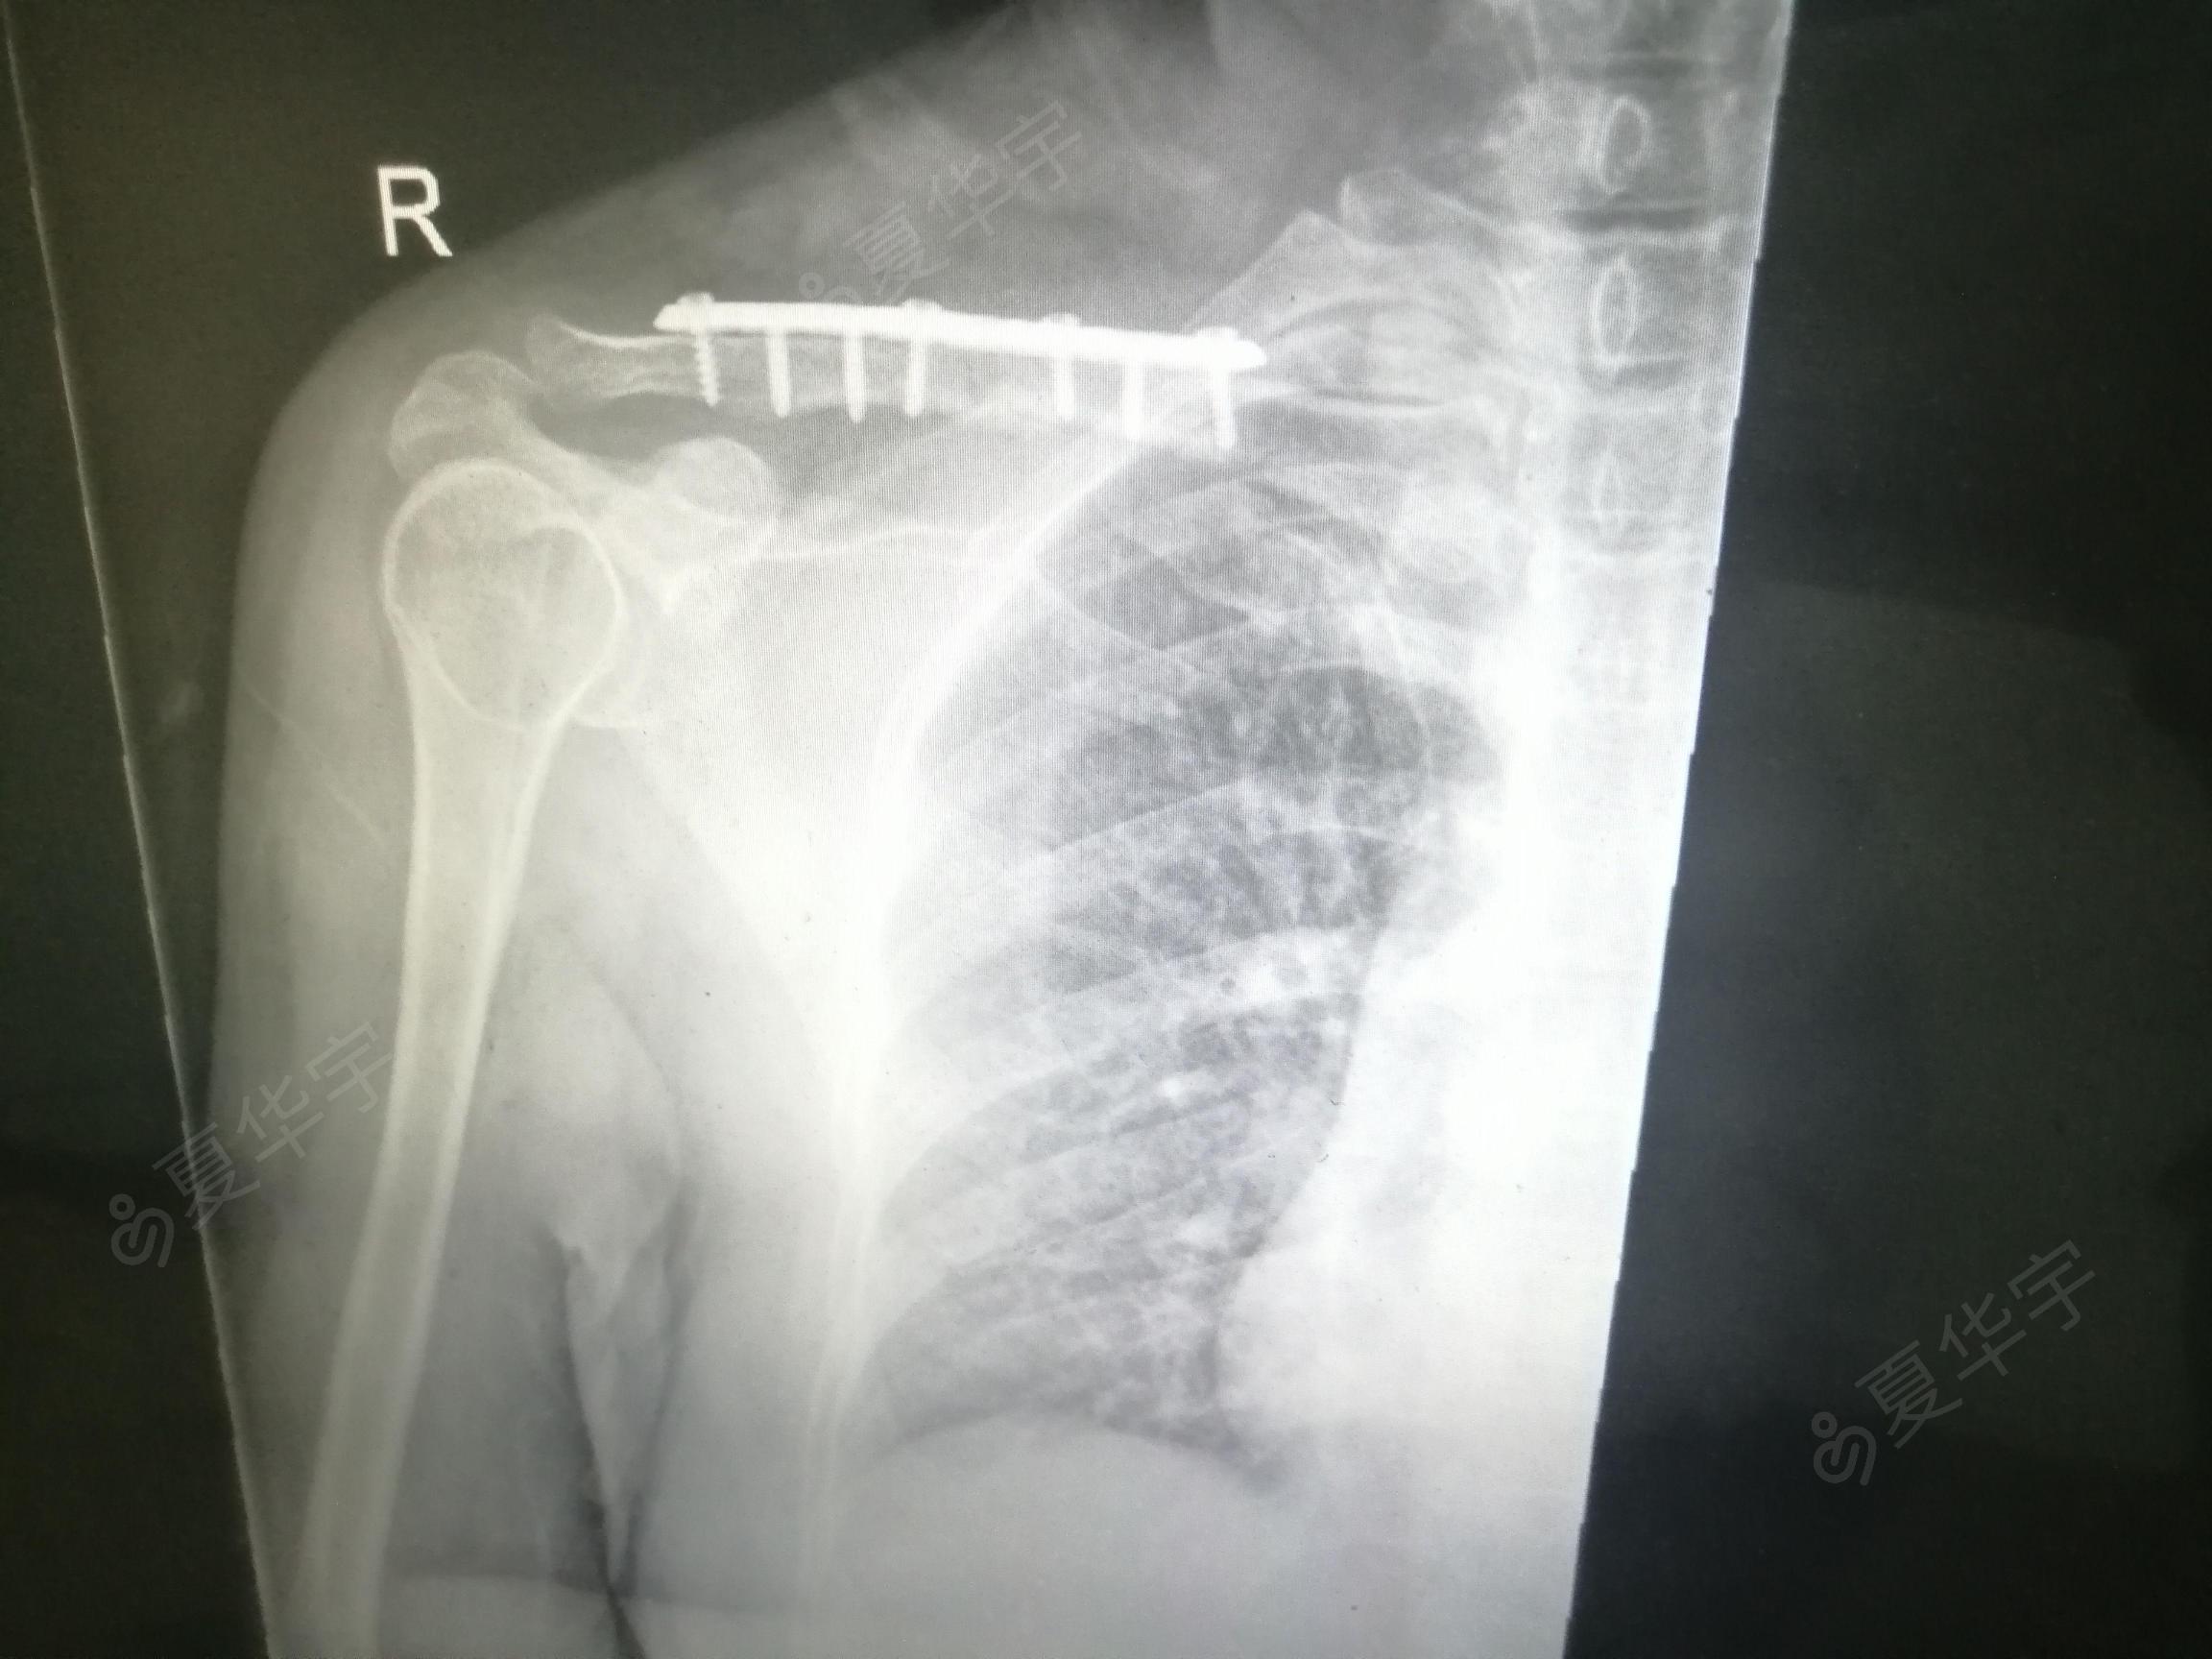

锁骨骨折有鼓包图片,锁骨错位重叠长好图片

右锁骨骨折治疗

锁骨骨折

锁骨骨折钢板图片

锁骨骨折图片